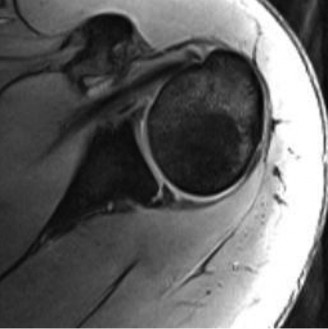

A 45-year-old carpenter presents with shoulder pain that has been ongoing for the last 3 months. He denies any significant injury. He describes night pain and significant discomfort at work. His imaging is shown in Figure 2–9. What is the most likely diagnosis?

Figure 2–9_From Shi LL, Mullen MG, Freehill MT, et al. Accuracy of Long Head of the Biceps Subluxation as a Predictor for Subscapularis Tears. _Arthroscopy 2015;32(4):615–619.

Discussion

The correct answer is (A). Medial subluxation of the biceps tendon as seen in this MRI is commonly associated with a tear of the subscapularis tendon which attaches to the lesser tuberosity. This patient’s pain may in part be attributable to the subscapular tear and this should be evaluated for during physical examination. Supraspinatus tears (Answer B) cannot be easily visualized on axial views and are not associated with medial biceps subluxations. A labral tear and ALPSA lesion (Answers C and D) are not seen on the images provided. The question stem and MRI are not suggestive of shoulder instability (Answer E). Objectives: Did you learn...? Diagnose and treat acute rotator cuff tears?